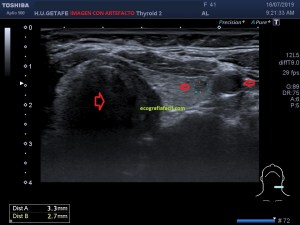

¿Pero cómo este artefacto degrada la imagen?, como una imagen vale más que mil palabras, te pongo dos imágenes de un corte del lóbulo tiroideo izquierdo, donde encontramos un nódulo pequeño. Observa y sobre todo presta atención a las flechas rojas. Son zonas de conflicto.

1

2

De los puntos de conflicto, principalmente, notamos el artefacto en dos, el nódulo y la arteria carótida izquierda, «manchada», más ecogénica de lo normal, (fig 1) cuando debería verse anecoica como en la figura 2. Sí, lo sé es muy sutil, pero es importante que la degradación de la imagen por pequeña que sea puede variar la fiabilidad diagnóstica, en este caso el nódulo de la figura 1 es menos nítido que el de la figura 2.